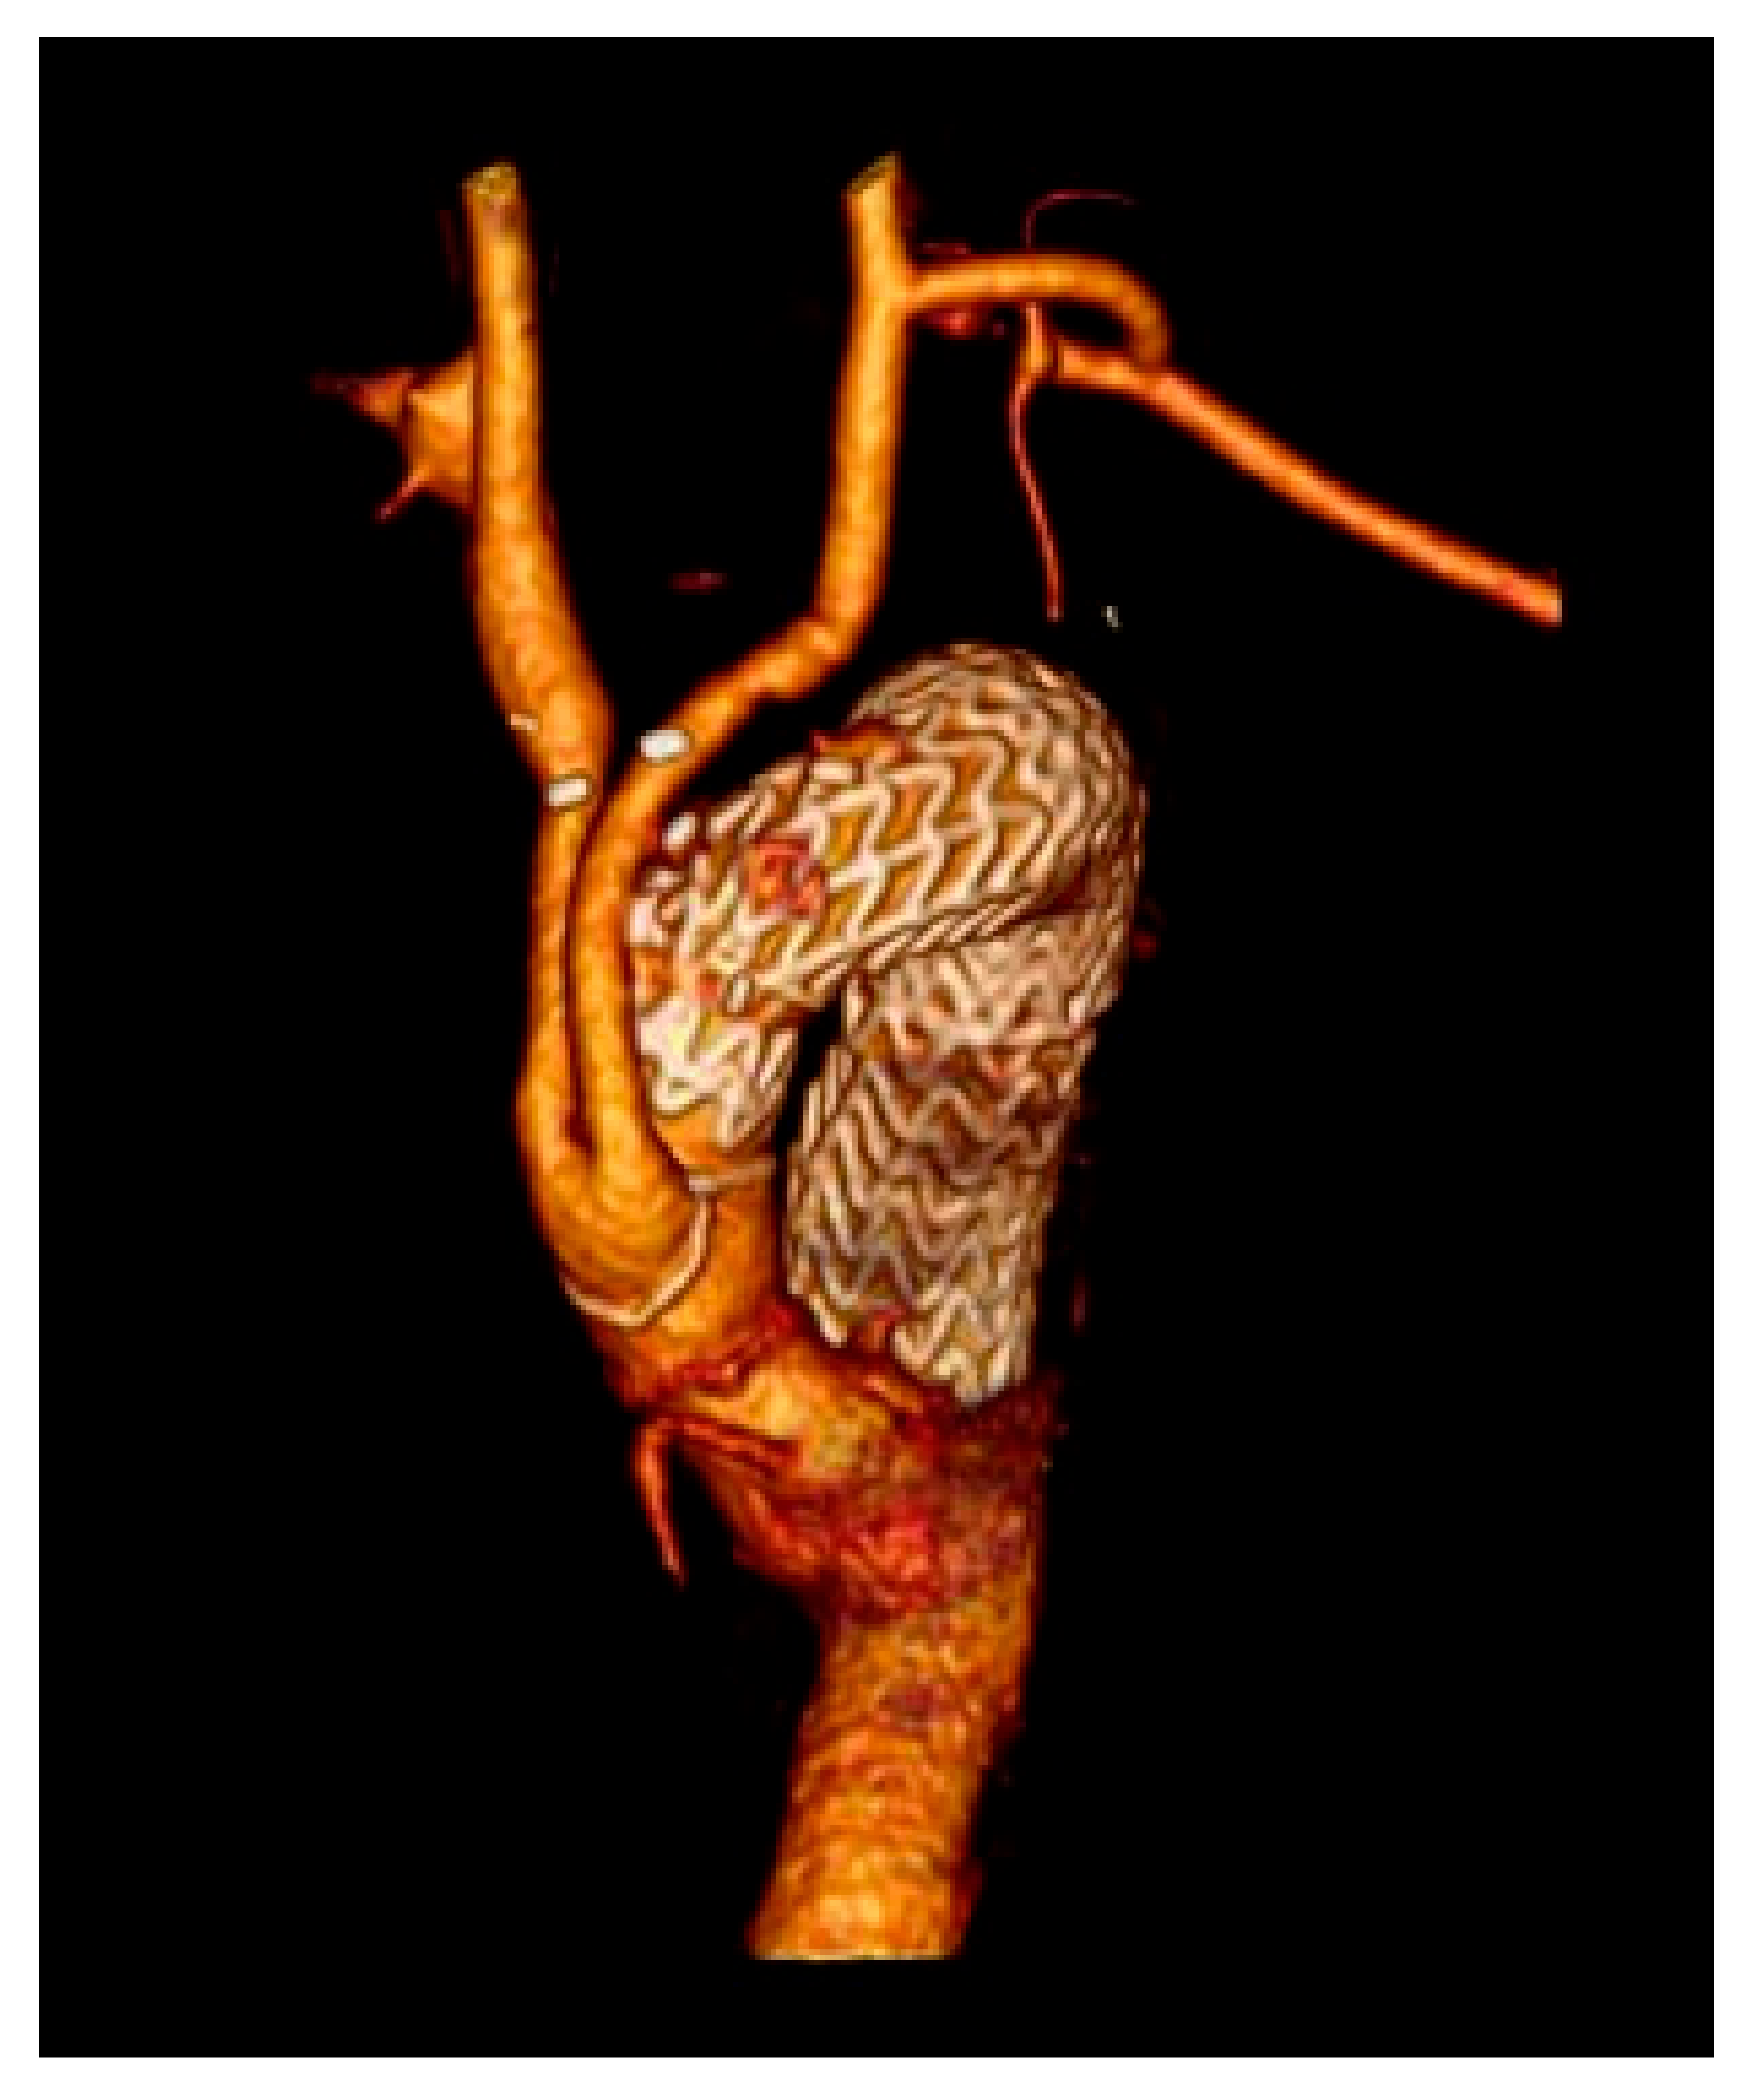

2.1. Surgical Technique

2.4. Branched Graft Position

2.7. Endovascular Technique